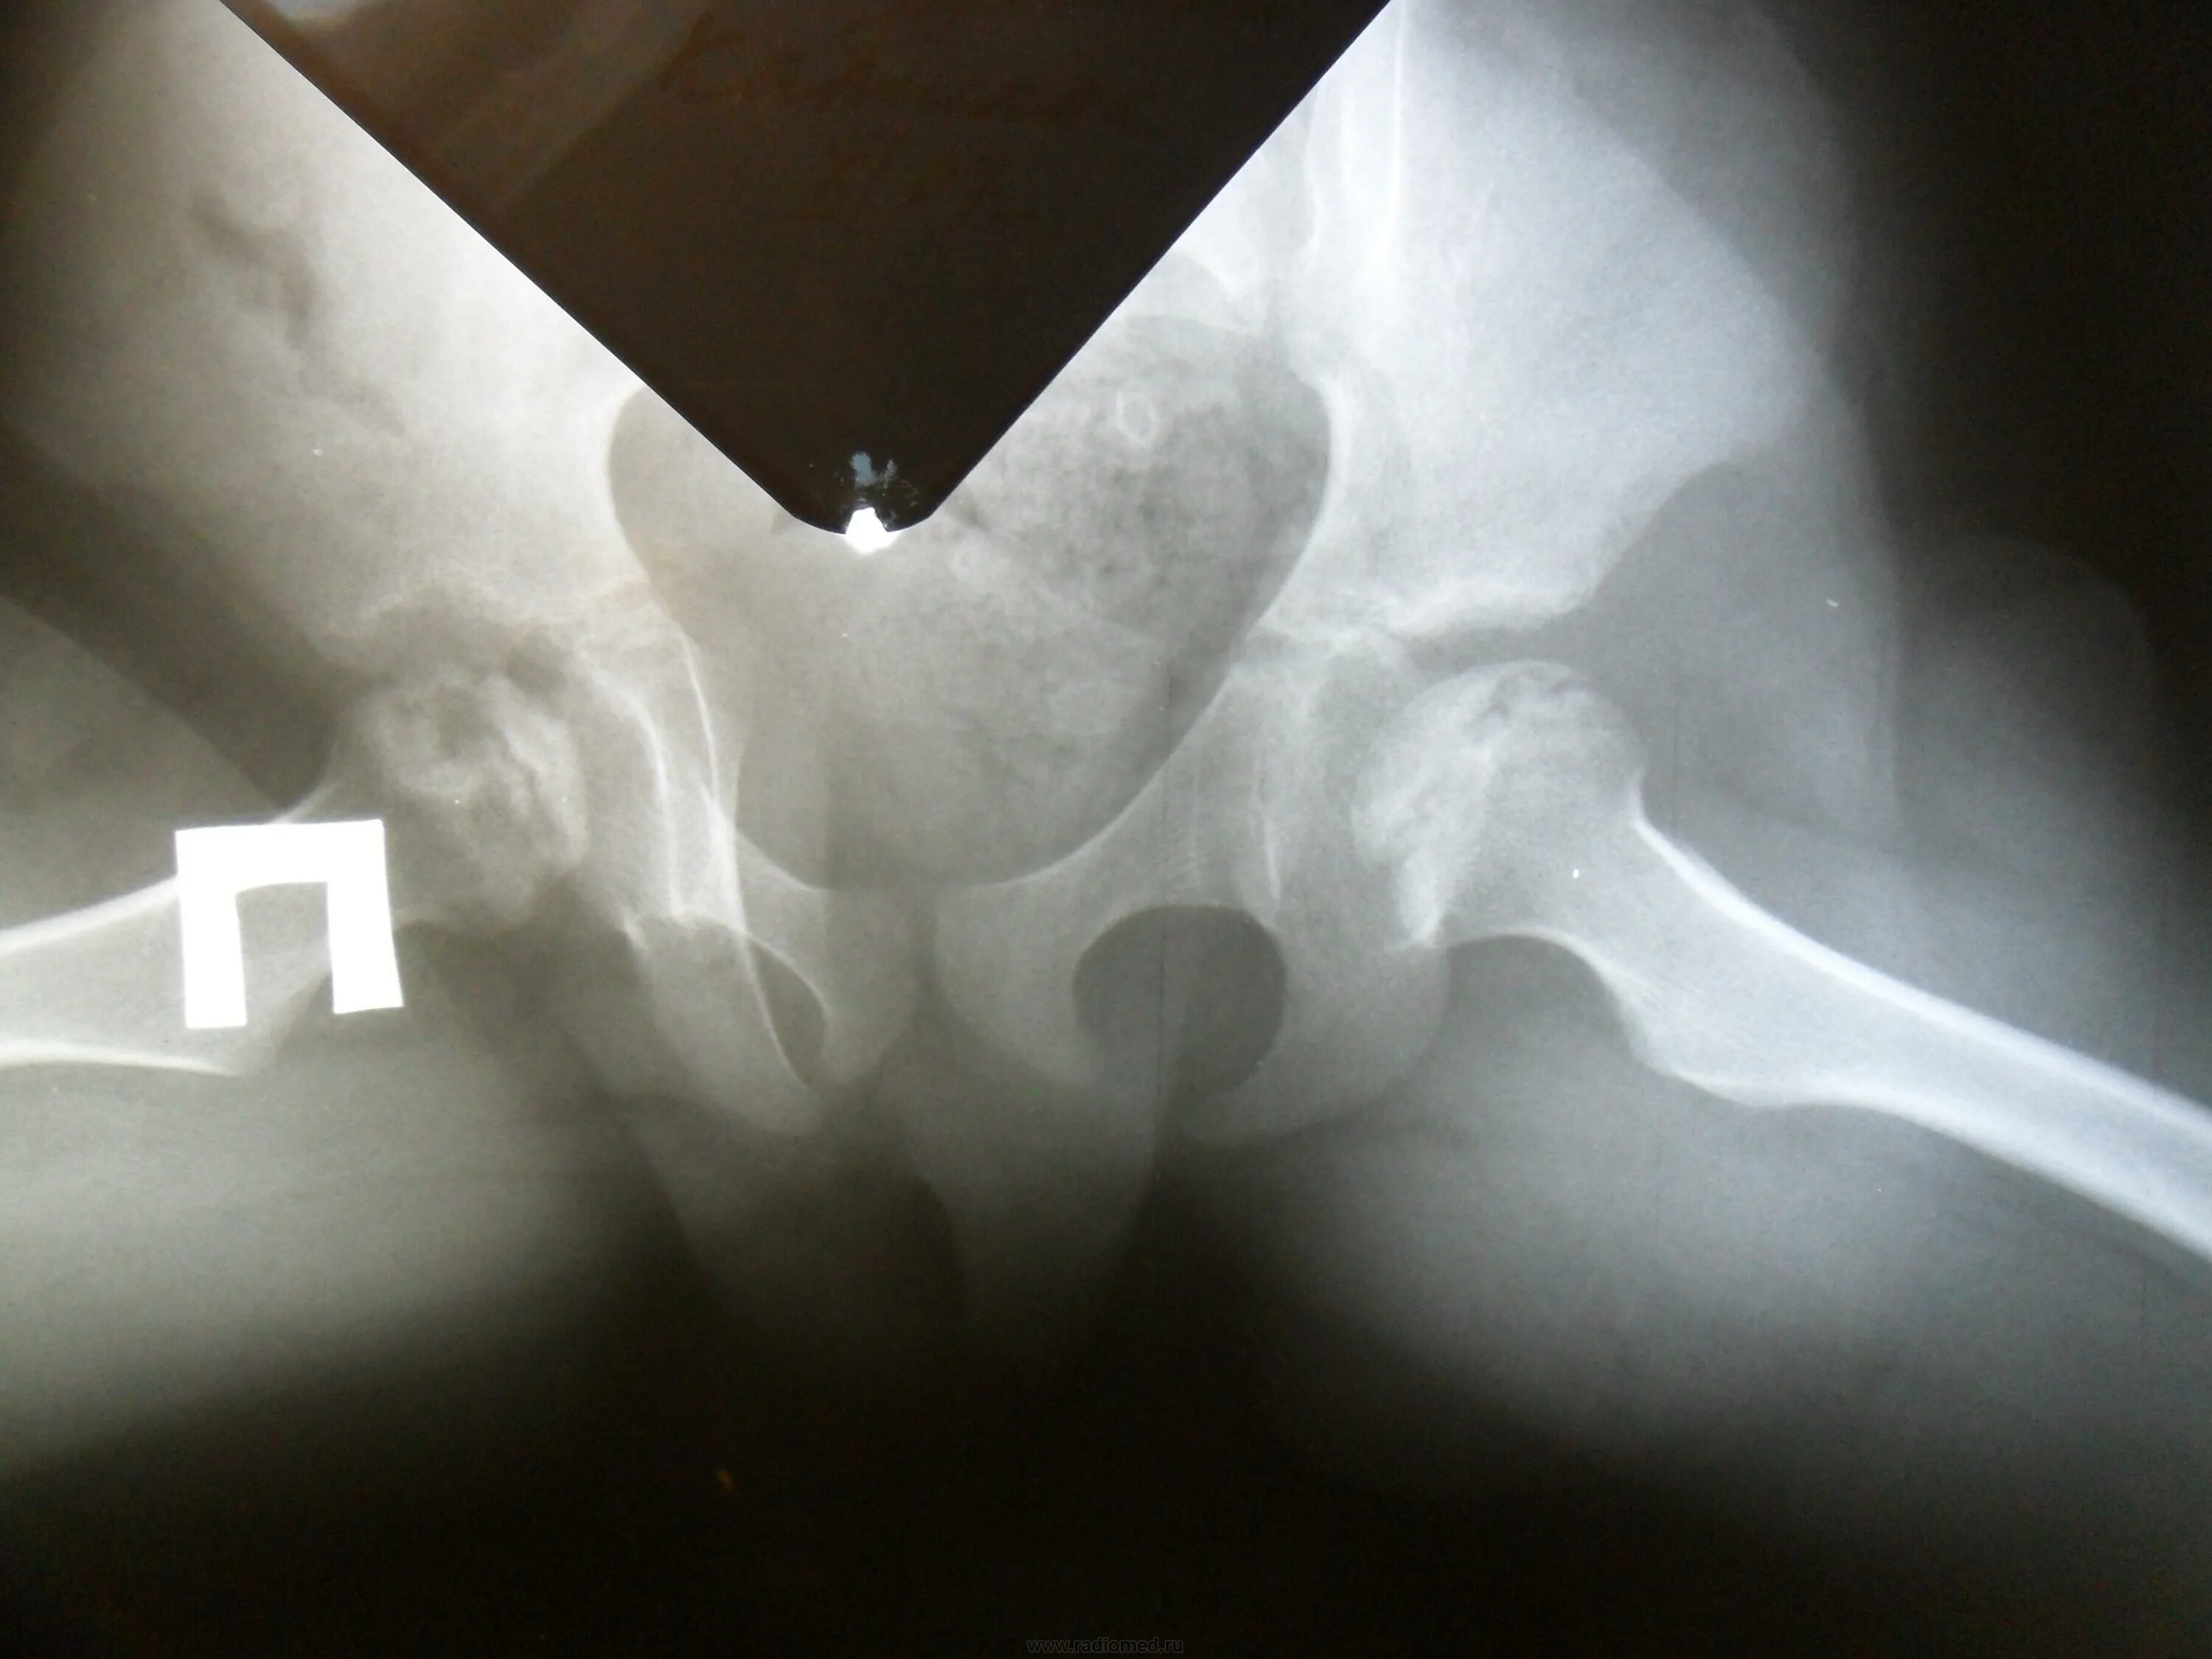

Делают ли узи тазобедренного сустава